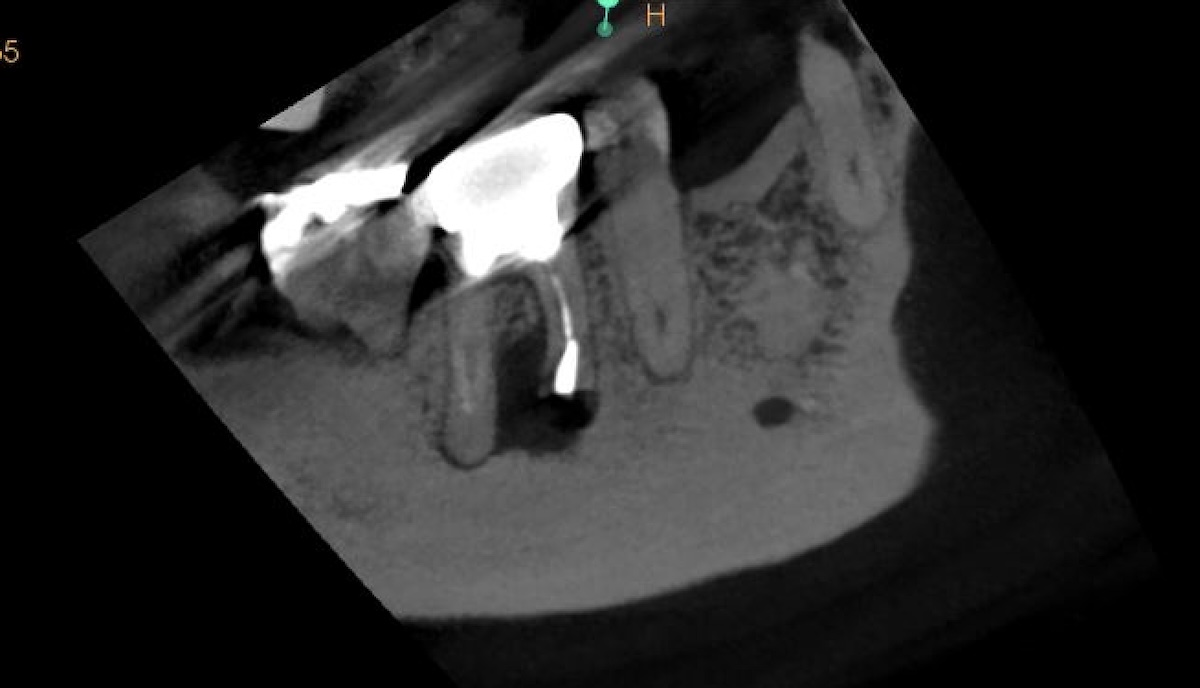

• 腫れを繰り返した奥歯(右上6番)。歯根端切除術で保存した症例。9ヶ月後の経過。

歯根端切除術の症例

2026.02.28

腫れを繰り返した奥歯(右上6番)。歯根端切除術で保存した症例。9ヶ月後の経過。